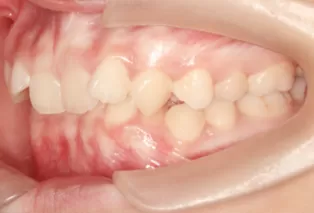

Intraoral photos